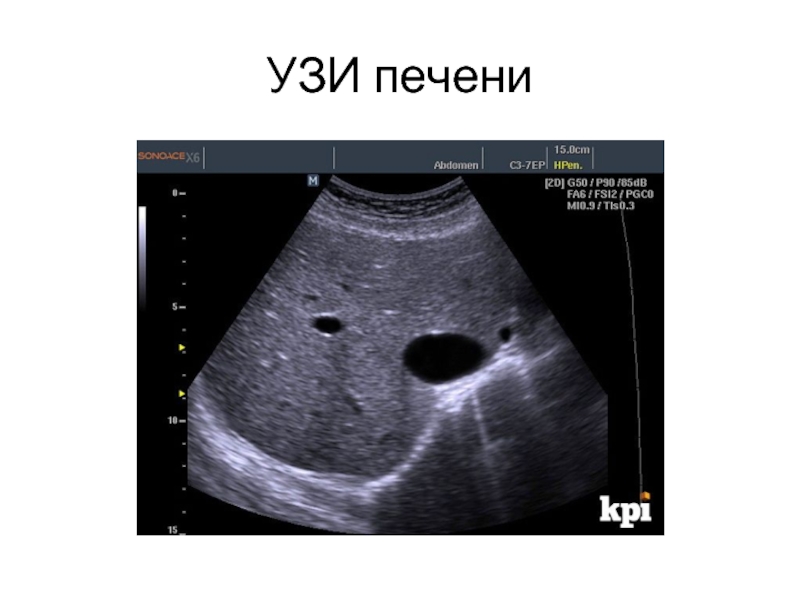

Слайд 12УЗИ печени